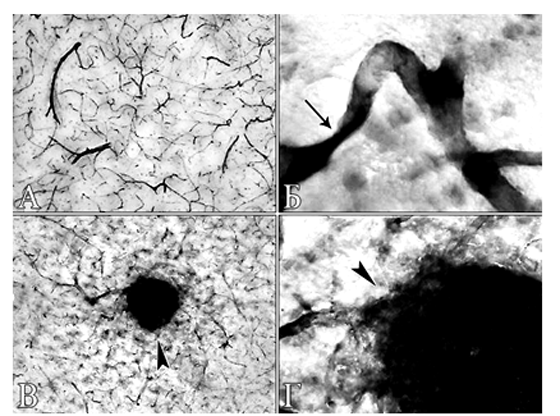

По полученным результатам, благодаря избирательному осаждению коричневого осадка фосфата свинца на эндотелии сосудов обеспечивалось избирательное, четкое и контрастное выявление микроциркуляторного русла мозга: артериол, венул и капилляров (рис. 1А).

Рис. 1. А – капиллярное русло сенсомоторной коры мозга крысы;

Б – суженный участок капилляра; В, Г – область кровоизлияния (стрелки).

Увеличение: ок. 10 (А-Г), об.10 (А,В); 40 (Г); 100 ( Б)

Кроме вышеописанных изменений в микроциркуляторном русле коры головного мозга, при поздних сроках алкоголизации как 5%, так и, особенно, 10% и 15% растворами этилового спирта, нами наблюдались множественные очаги кровоизлияний (рис.1 В, Г).